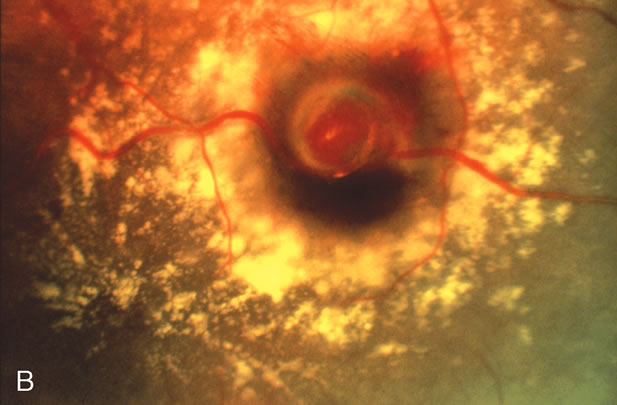

Vitrectomy with surgical evacuation of submacular hemorrhage may be indicated when there is a reasonable chance of recovery of some degree of central vision (Fig. 7).21–26 In the eye in which blood that has been under the macula for more than 2 weeks, there is little possibility of visual recovery because of blood toxicity to the photoreceptors. Many authorities consider surgical evacuation of submacular blood when the blood has been present under the macula for 2 weeks or less, preferably less than 7 days. The technique involves a pars plana vitrectomy, followed by a small perforation near the edge of the blood to gain access to the subretinal space. TPA is usually employed to help lyse the blood, thus facilitating its removal with minimal damage to the photoreceptors. The blood is removed using a subretinal cannula; some models feature a double-barreled shaft that allows the injection of fluid into the subretinal space through one barrel and the removal of blood through the other barrel. Some authors note that the use of a bubble of perfluorocarbon liquid on the surface of macula helps express the blood from beneath the macula.

Fig. 7. A. Color fundus photograph of a macroaneurysm causing subretinal and sub-ILM hemorrhage involving the macula. B. Illustration of the spatial relationship between the submacular blood and sub-ILM blood. C. During vitrectomy surgery, a subretinal cannula is used to inject tissue plasminogen activator into the blood clot. D. After the blood is allowed to lyse over the course of 40 minutes, it is removed using a subretinal cannula.